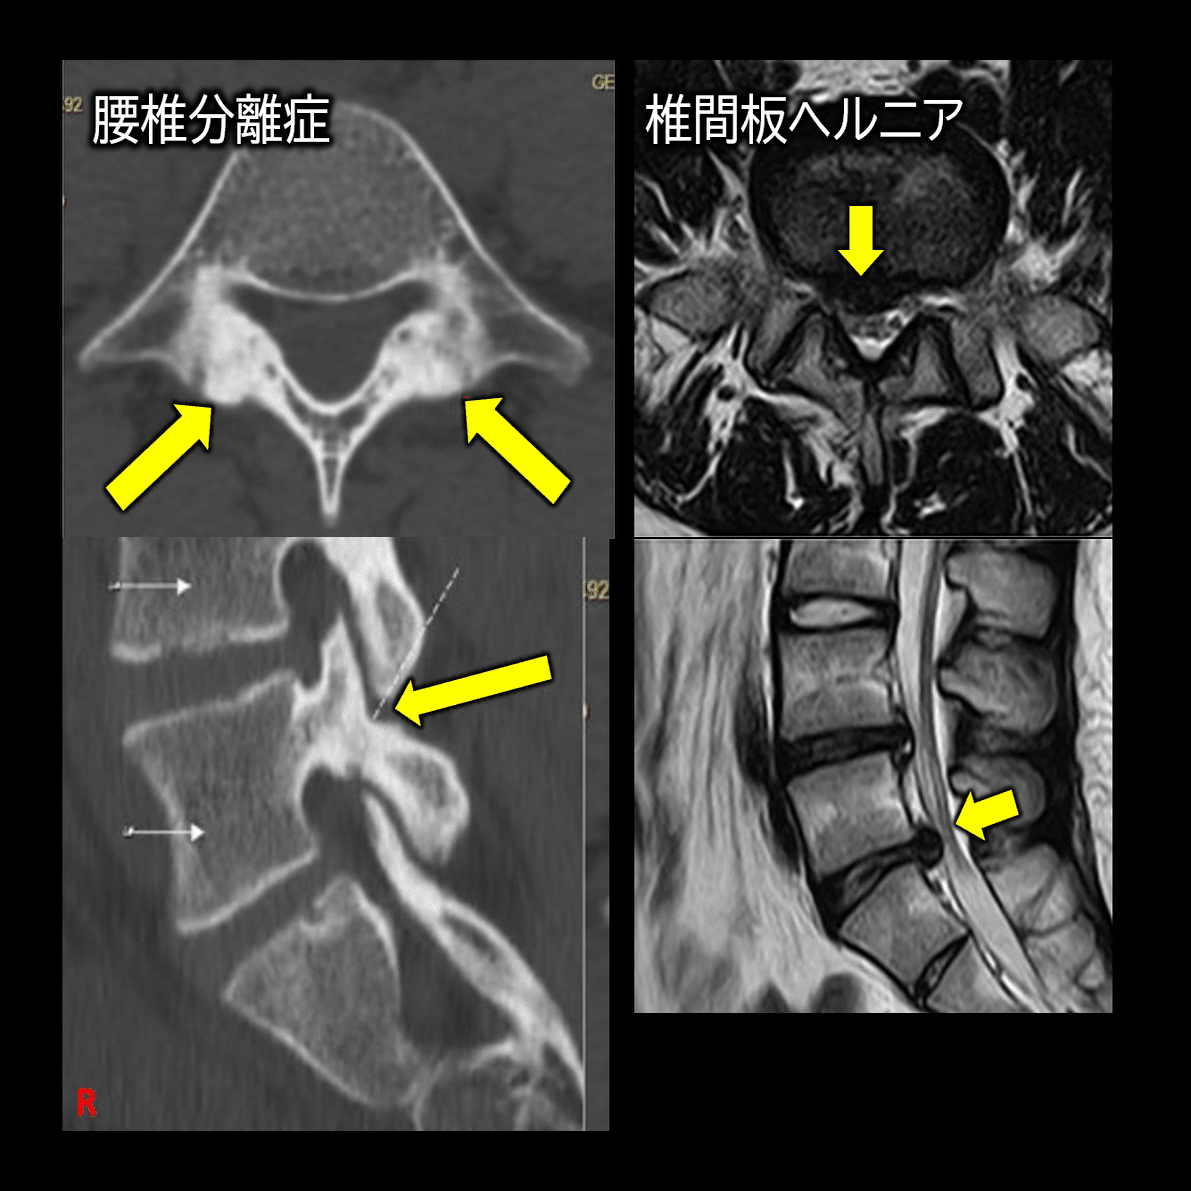

- 腰椎椎間板ヘルニア

- 腰椎分離症

腰椎椎間板ヘルニア:Fukunaga T, Sasaki M, Bamba Y, Utsugi R, Matsumoto K, Umegaki M. A rare case of lumbar disc herniation mimicking lumbar discal cyst after percutaneous endoscopic lumbar discectomy. Interdiscip Neurosurg. 2021;25:101131.

これらはマッサージやストレッチ、エクササイズで改善しうるものではないため、医療機関での画像検査を要する腰痛かどうかの見極めが必要不可欠です。

以下に簡単に所見をまとめましたので、ご参照ください。